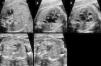

Thus, identification of congenital heart defects is one of the main goals of the morphology ultrasound examination (18–22 weeks). Still, the rate of detection of congenital heart defects by assessment of the four chambers of the foetal heart is inadequate.12–14 To improve results we propose performing the extended basic foetal cardiac examination proposed by Yagel (foetal abdomen, four-chamber view, great vessel outflow tracts, and thoracic three-vessel view; Fig. 1).15

Extended basic examination proposed by Yagel. Plane 1: abdominal view. Plane 2: four-chamber view. Plane 3: five-chamber view, aortic root. Plane 4: pulmonary artery bifurcation view. Plane 5: three vessel and trachea view. A: aorta; AD: right atrium; AI: left atrium; APD: right pulmonary artery; API: left pulmonary artery; E: stomach; H: livery; P: pulmonary artery; S: spine; SA: aortic aortic root; T: trachea; VCI: inferior vena cava; VCS: superior vena cava; VD: right ventricle; VI: left ventricle; VP: pulmonary veins.

We screened for structural malformations with a morphology ultrasound examination performed at 20 weeks (18–22 weeks) in the prenatal diagnosis unit of the Hospital Universitario de Valme. The examination lasted a minimum of 20min and was performed by one of three highly qualified sonographers (with over 5 years’ full-time experience in obstetric ultrasound) in compliance with the recommendations of the Sociedad Española de Obstetricia y Ginecología (Spanish Society of Obstetrics and Gynaecology)16 and the Royal College of Obstetricians and Gynaecologists17 for the performance of structural ultrasound examinations. The screening for congenital heart defects at 20 weeks of gestation involved an extended basic foetal heart examination15 of five transverse planes (Fig. 1). The ultrasound machines used for the examination were 1 Philips HDI 4000 system (Philips Medical Systems) and 1 GE E8 (General Electric).